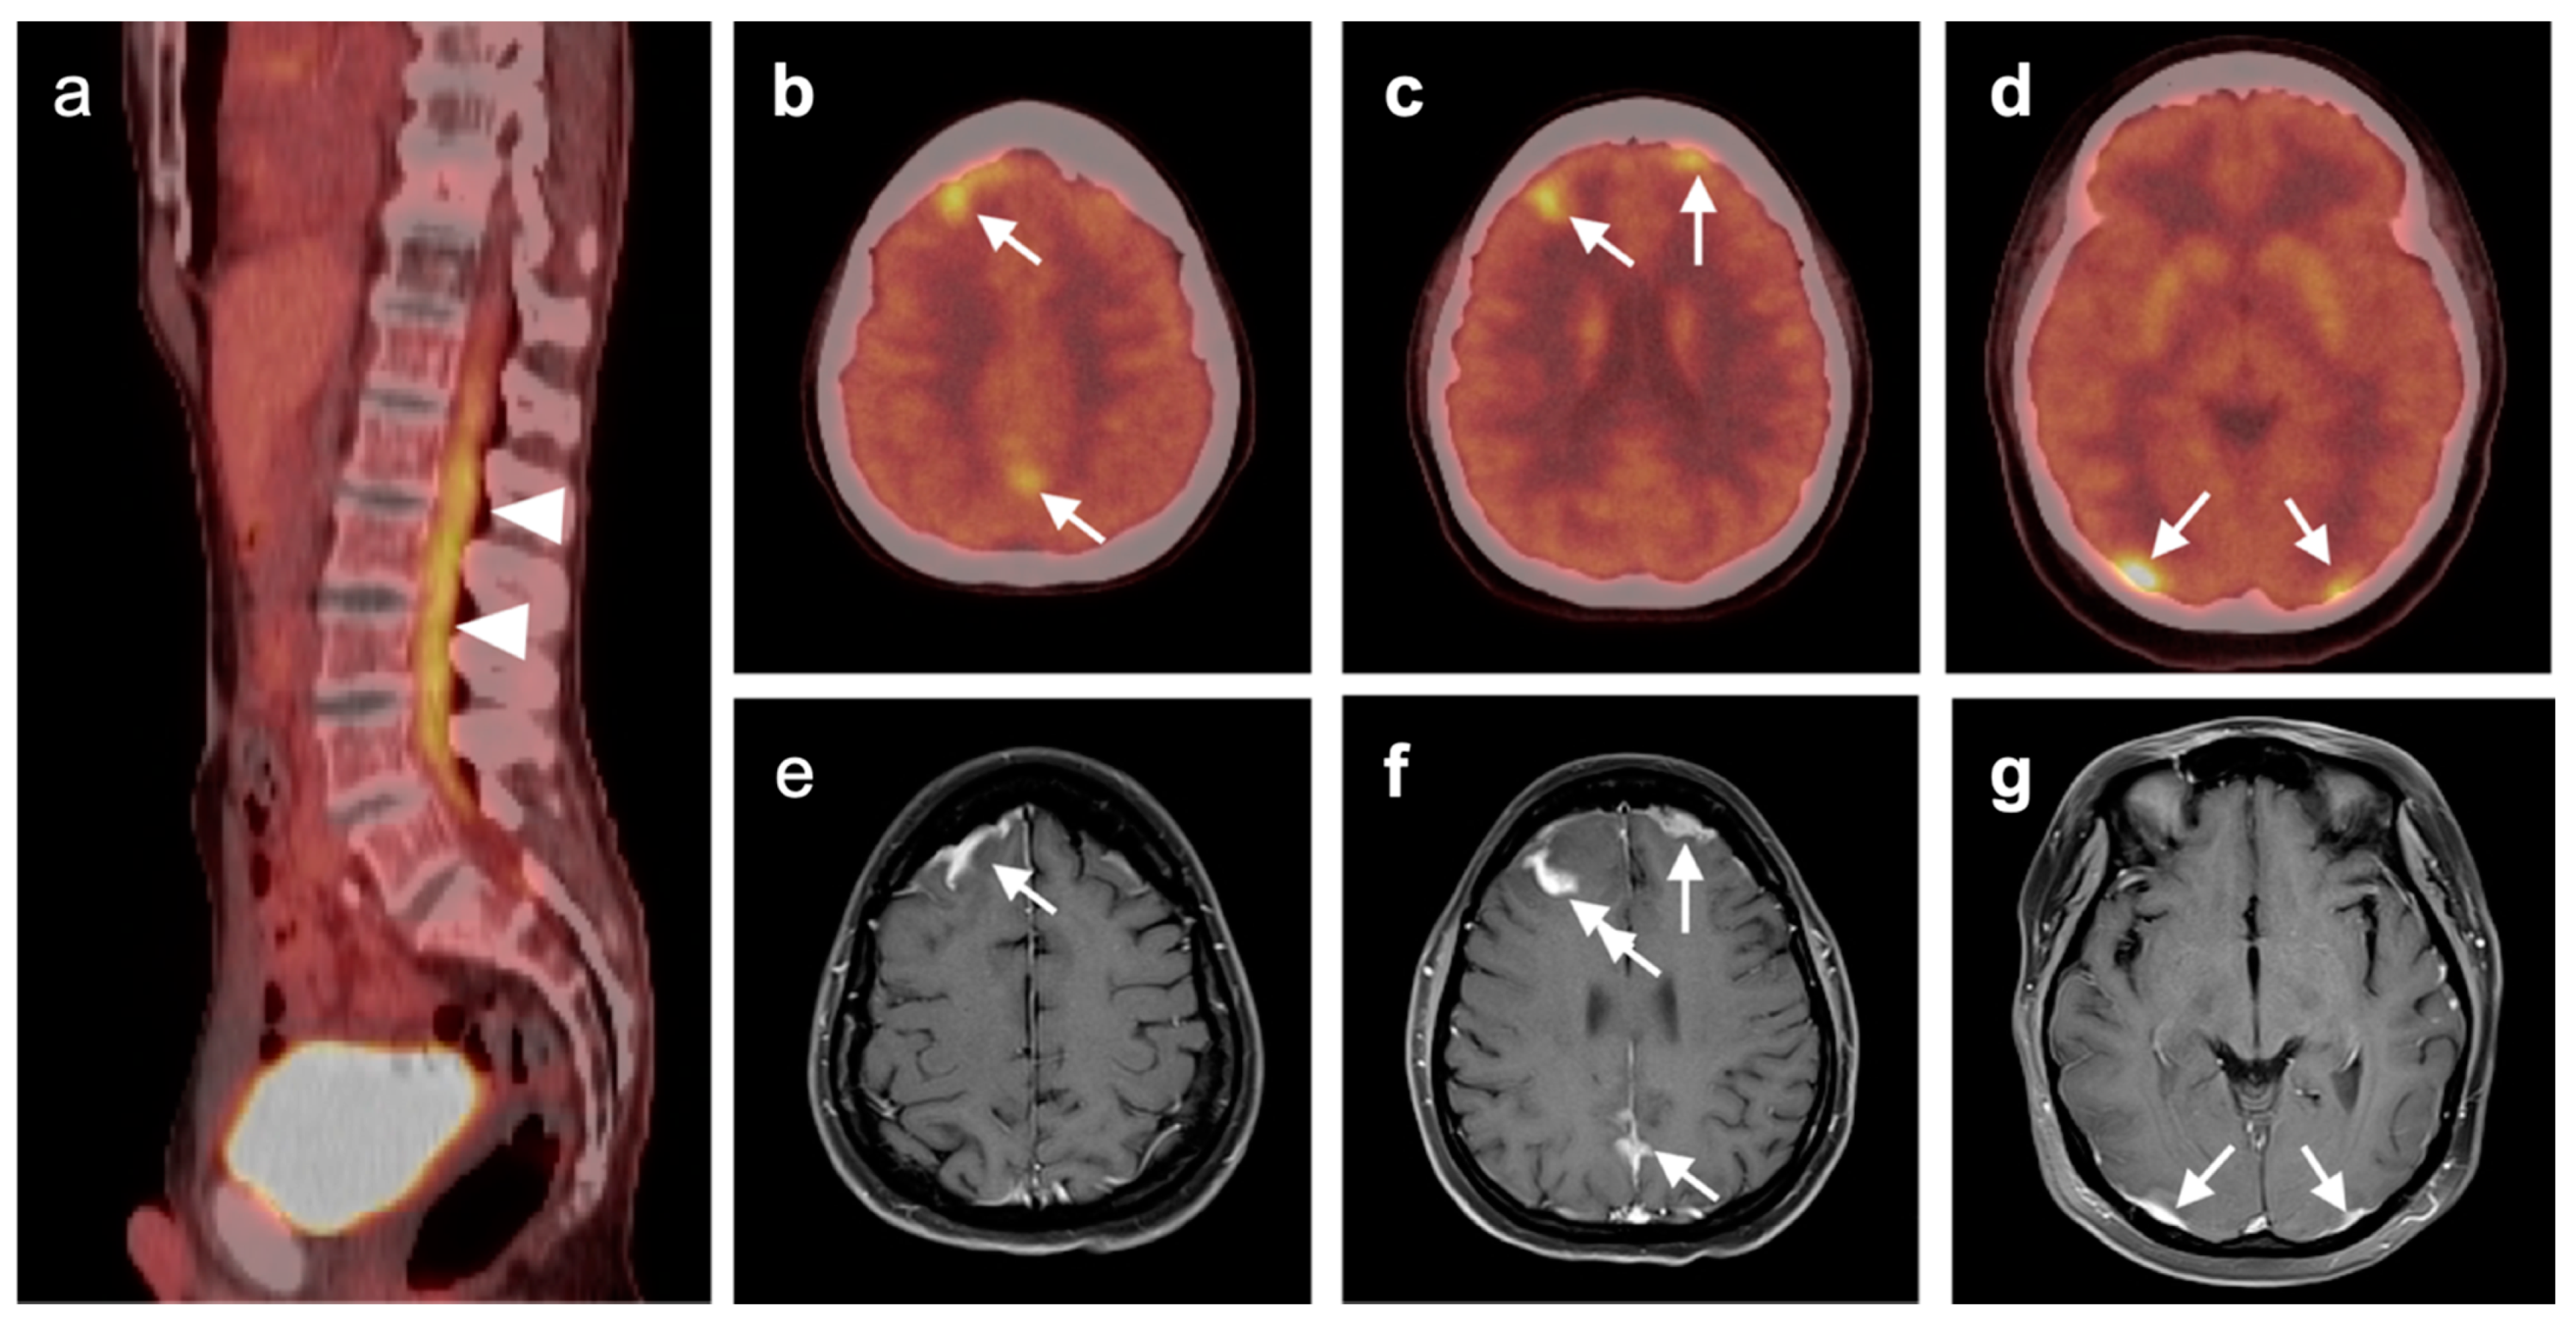

3.5. Brain Metastases

- Galldiks, N.; Langen, K.-J.; Albert, N.L.; Chamberlain, M.; Soffietti, R.; Kim, M.M.; Law, I.; Le Rhun, E.; Chang, S.; Schwarting, J.; et al. PET imaging in patients with brain metastasis-report of the RANO/PET group. Neuro-Oncology 2019, 21, 585–595. [Google Scholar] [CrossRef]

- Unterrainer, M.; Galldiks, N.; Suchorska, B.; Kowalew, L.C.; Wenter, V.; Schmid-Tannwald, C.; Niyazi, M.; Bartenstein, P.; Langen, K.J.; Albert, N.L. 18F-FET PET Uptake Characteristics in Patients with Newly Diagnosed and Untreated Brain Metastasis. J. Nucl. Med. 2016, 58, 584–589. [Google Scholar] [CrossRef] [PubMed]

- Horky, L.L.; Hsiao, E.M.; Weiss, S.E.; Drappatz, J.; Gerbaudo, V.H. Dual phase FDG-PET imaging of brain metastases provides superior assessment of recurrence versus post-treatment necrosis. J. Neurooncol. 2011, 103, 137–146. [Google Scholar] [CrossRef]